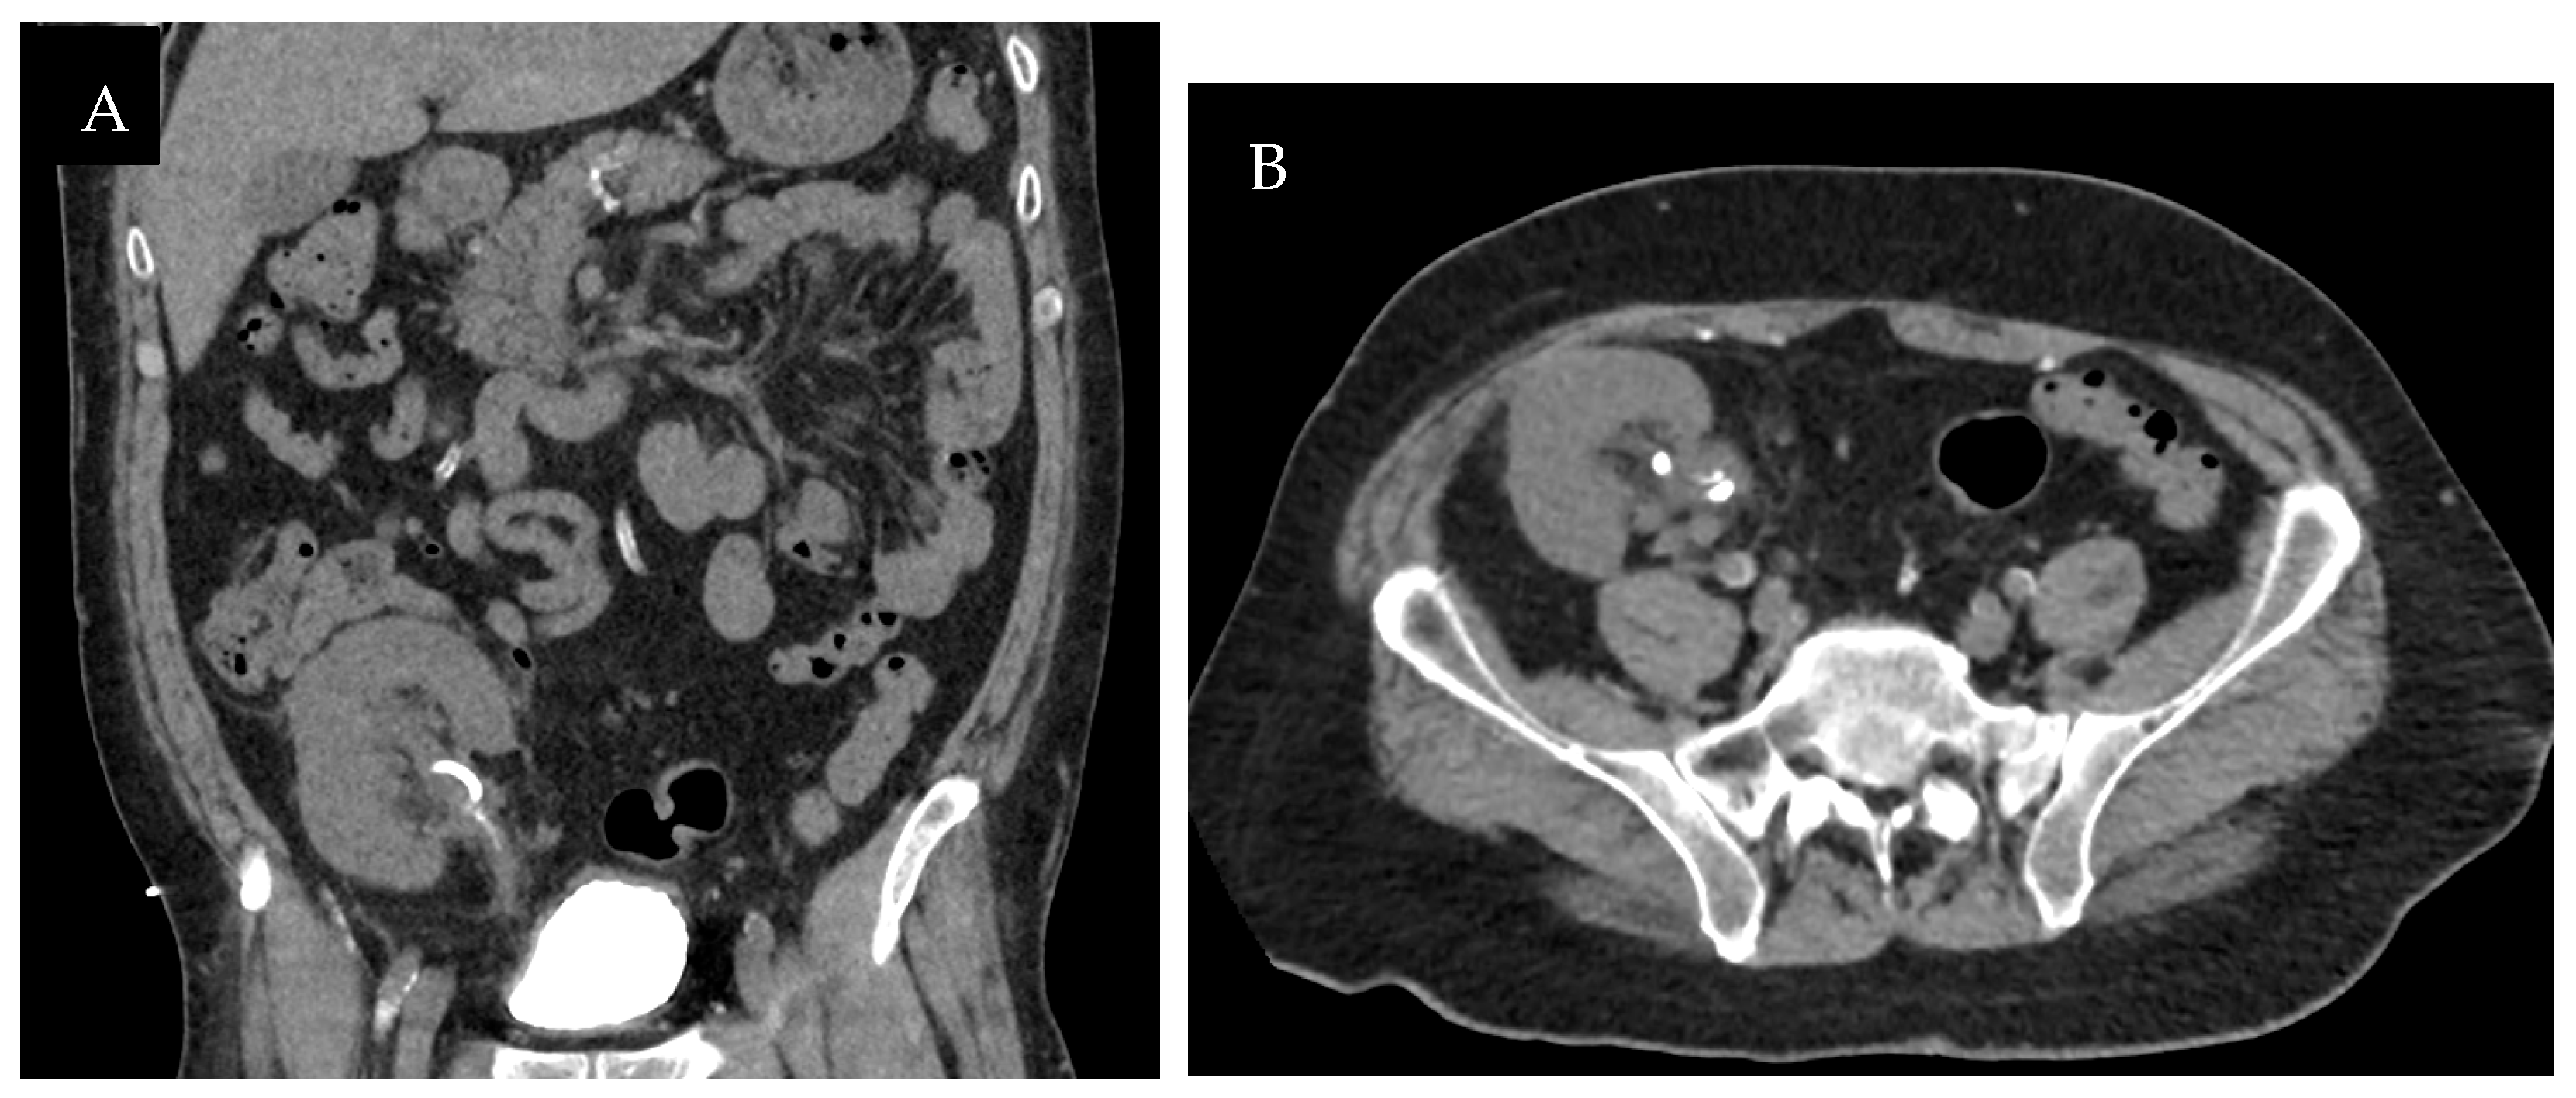

The patient’s renal function remained stable over the next year (creatinine 1.0–1.3 mg/dL, eGFR 53–78 mL/min/1.73 m2). However, the patient experienced three urinary tract infections during this time: the first was Escherichia coli and the latter two Klebsiella pneumoniae. An ultrasound at nearly 1-year post-transplant demonstrated an echogenic structure in the renal pelvis concerning for a renal calculus (Figure 4). A follow-up CT scan demonstrated an irregular soft-tissue density with rim calcification at the ureteropelvic junction measuring 5 × 3.5 centimeters and minimal transplant kidney pelvicaliectasis (Figure 5). Ureteroscopy was attempted but unsuccessful due to difficulty cannulating the ureteral orifice at the bladder dome.

Figure 5. One-year post-transplantation non-contrast CT coronal (A) and axial (B) images demonstrated an irregular soft-tissue density with rim calcification at the ureteropelvic junction and proximal ureter measuring 5 × 3.5 centimeters, as well as minimal transplant kidney pelvicaliectasis.